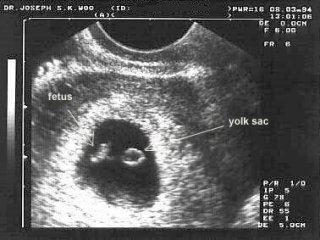

Στην 1η επίσκεψη σας (μετά από ένα θετικό τεστ κυήσεως) η ιατρός Κ. Παπακωνσταντίνου θα επιβεβαιώσει την κύηση σας εκτελώντας ένα διακολπικό υπερηχογράφημα και πιθανά να ζητήσει εξέταση αίματος για να προσδιοριστούν με ακρίβεια τα επίπεδα της β-χοριακής γοναδοτροπίνης, της ορμόνης της κύησης (β-hCG). Μερικές φορές θα χρειαστεί να επαναλάβει το υπερηχογράφημα σε 1-2 εβδομάδες για να σιγουρευτεί για τη θετική καρδιακή λειτουργία του εμβρύου και την καλή ανάπτυξη του. Θα λάβει ένα πλήρες προσωπικό και οικογενειακό ιστορικό και θα σας περιγράψει με λεπτομέρεια το πλάνο παρακολούθησης της εγκυμοσύνης σας (πότε θα γίνουν οι επισκέψεις και τι θα περιλαμβάνουν). Επίσης, θα σας σώσει συμβουλές όσον αφορά τη διατροφή σας, τα συμπληρώματα διατροφής και τι συνήθειες πρέπει να συνεχίσετε ή να αποφύγετε. Το πλάνο θα σας δοθεί και γραπτά ώστε να έχετε πρόσβαση σε αυτό οποτεδήποτε και μελετώντας το να καταγράψετε τυχόν απορίες για να συζητήσετε στις επόμενες επισκέψεις με την ιατρό. Γενικά, θα σας βλέπει μια φορά το μήνα, ενώ η συχνότητα των επισκέψεων θα αυξηθεί (ανά 2 εβδ. και ανά 1 εβδομάδα) τον τελευταίο μήνα της κύησης.